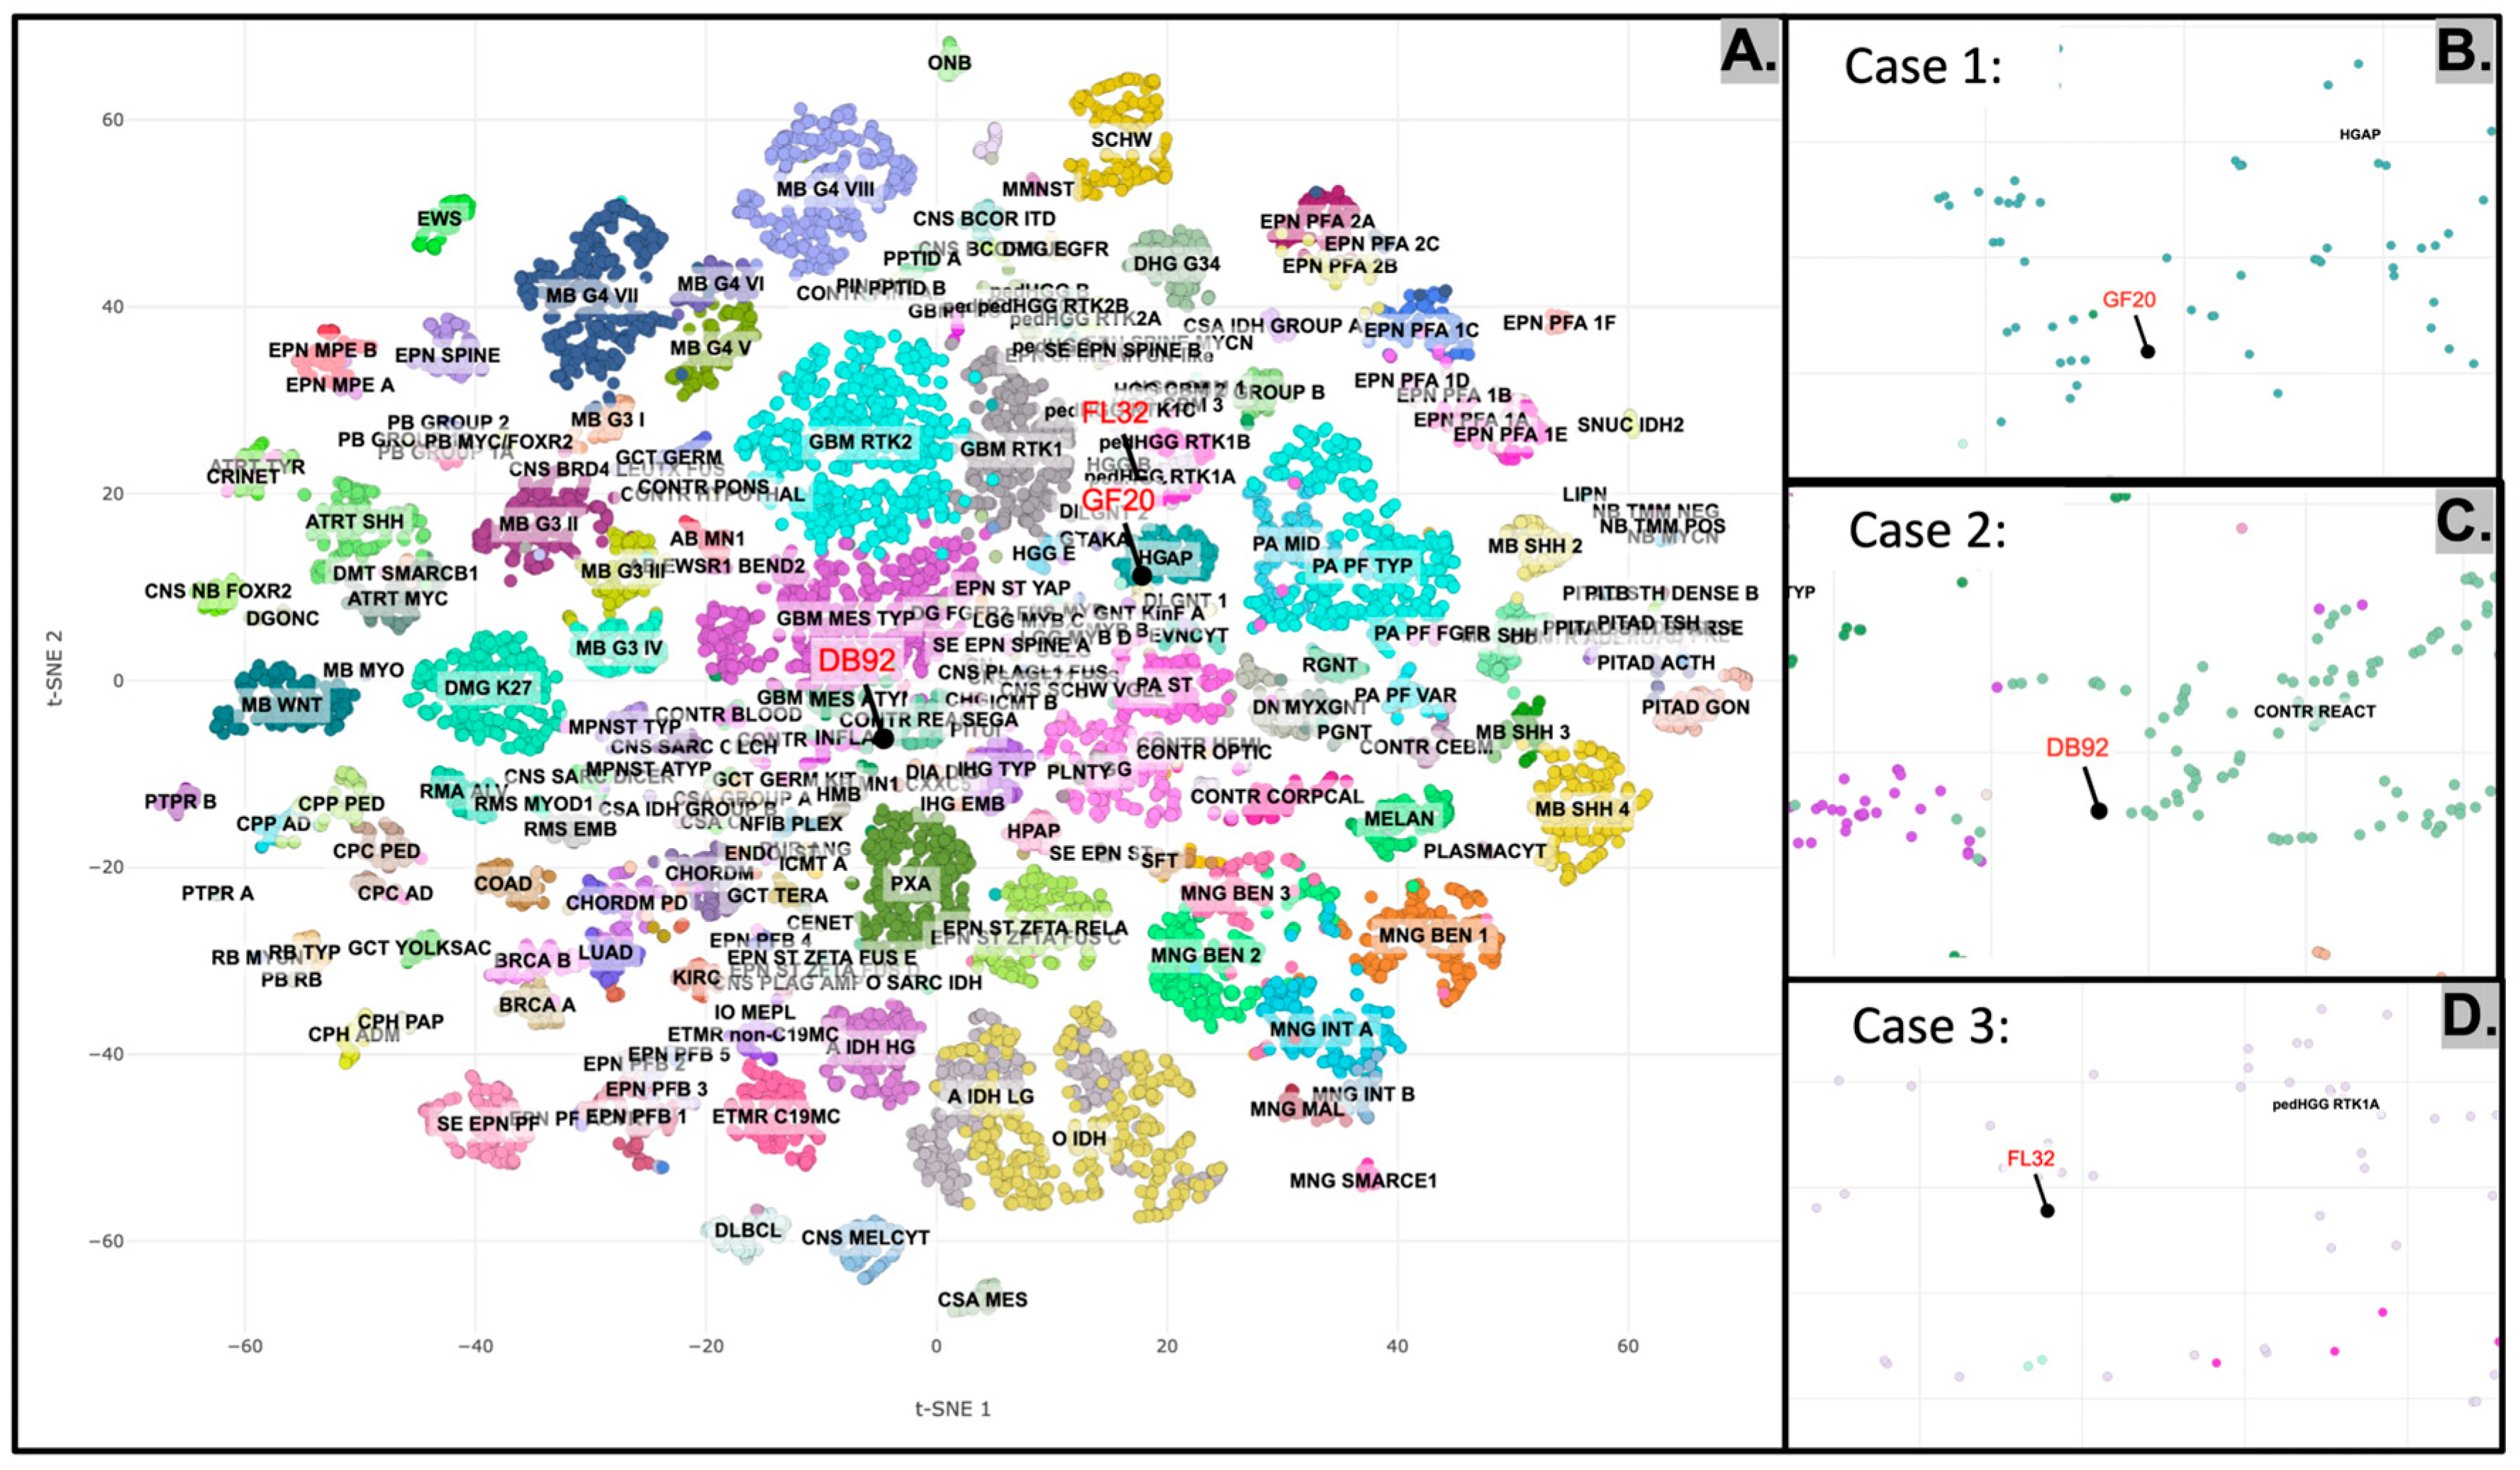

2.5. DNA Methylation Profiling of the Tumors

2.2.1. Case 1

2.2.2. Case 2

2.2.3. Case 3